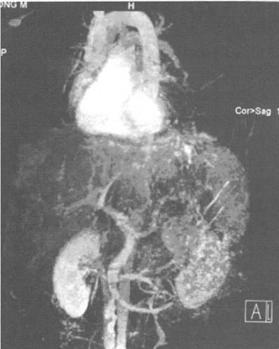

巴德-吉亚利综合征(Budd-Chiari syndrome,BCS)是一种肝胆外科疾病,由于各种原因所致的肝静脉和邻近下腔静脉狭窄闭塞,致使肝静脉和下腔静脉血液回流障碍。巴德-吉亚利综合征临床表现为产生肝大及疼痛、腹水,肝脏功能障碍等。